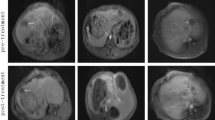

For the TUS + MB + HT group, two kinds of pathological changes were observed. First, a diffuse hemorrhage and focal thrombus were observed in the portal areas. When the hemorrhage occurred in the connective tissue layer of the portal canals, it often formed a circular and sleeve-like hematoma that surrounded the portal veins, although the structure of the portal wall appeared intact (Fig. 6a). Second, the hepatocytes were swollen and squeezed the sinuses around them (Fig. 6b). Some erythrocytes had accumulated in the portal areas in the MB + HT group (Fig. 6c) and NS + HT group (Fig. 6d), with a higher number of erythrocytes in the MB + HT group than in the NS + HT group. For the MB + sham group, normal liver cells that were arranged in plates with visible sinusoids in between were observed (Fig. 6e).

Pathological images of treated liver tissues with H&E staining: a extensive sleeve-like hematoma at the portal areas in the TUS + MB + HT group; b swelling hepatocytes compressed and shrank the intervening sinusoids in the TUS + MB + HT group; c some erythrocytes accumulated in the portal areas in the MB + HT group; d some erythrocytes accumulated in the portal areas in the NS + HT group; and e structure of the liver cells and visible sinusoids in the MB + sham group appeared normal